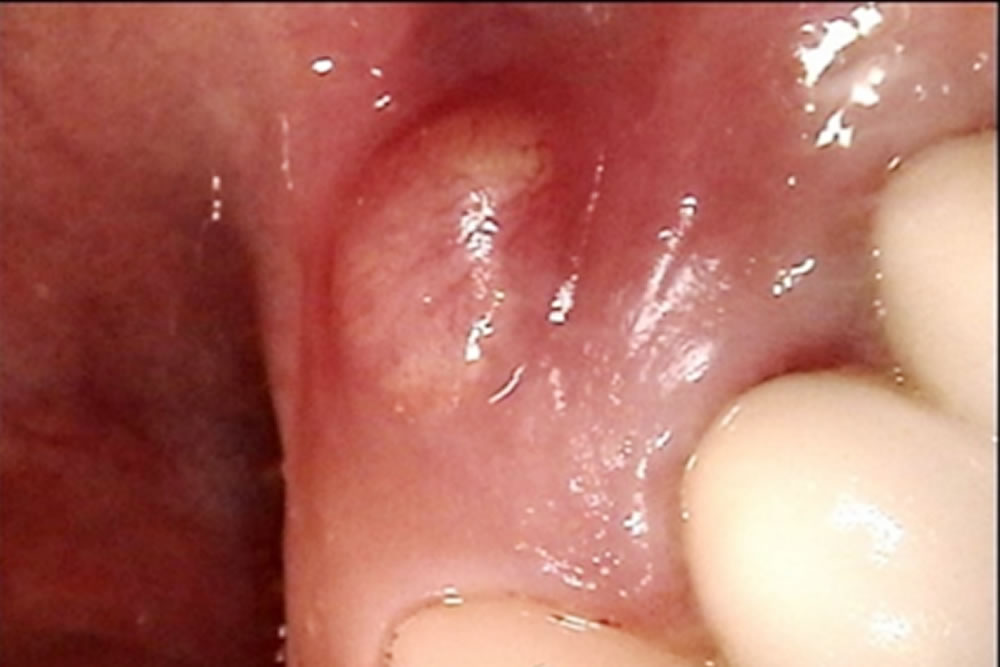

こちらの患者さまは他院で入れたブリッジの土台の歯(4番目の歯)の歯茎が腫れてきてしまったため、治療を行うことになりました。